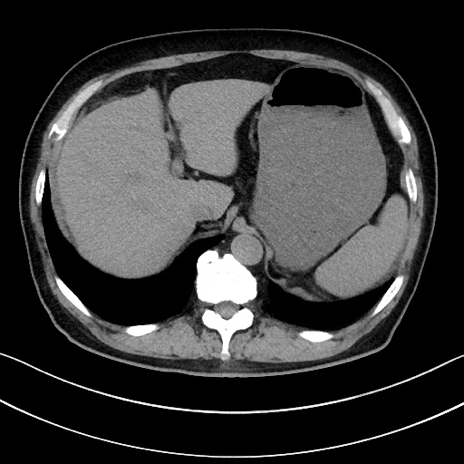

症例15(横断像)

【症例】70歳代男性

【主訴】腹痛

【現病歴】今朝から腹痛あり。全体的に痛い。特に左上の方。排ガスが今日はない。冷や汗が出る。

【既往歴】直腸癌術後

【身体所見】左側腹部〜上腹部に圧痛あり。腹膜刺激症状明らかなではない。軽度反跳痛。左下腹部に術後瘢痕あり。

【データ】WBC 7700、CRP 0.02